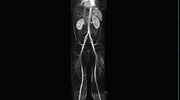

• Bauchgefäße

• Erfassung und Verlaufskontrolle bei arteriellen Aneurysmen (Aussackungen der Arterien), vor allem der Bauchaorta

• Darstellung von Gefäßengen an Nierenarterien, Baucharterien und Becken-/Beinarterien

MR-Angiografie (MRA)

• MR-Angiographie mit Kontrastmittel

• Erfassung arterieller und venöser Gefäße/Bypässe aller Körperregionen mit 3D-Rekonstruktion